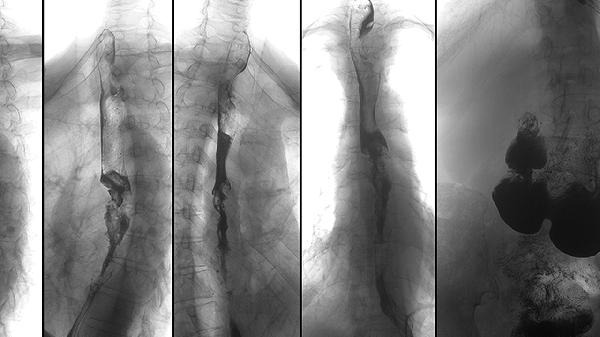

建议定期监测骨龄变化,每半年拍摄左手X光片评估骨骺闭合程度。日常避免负重劳动和过度节食,骑行时调整车座高度防止脊柱受压。可尝试瑜伽中的山式、猫牛式等体式拉伸椎间隙,配合足底按摩刺激生长相关穴位。保持积极心态,身高并非衡量个人价值的唯一标准,青少年时期更应关注综合素质发展。